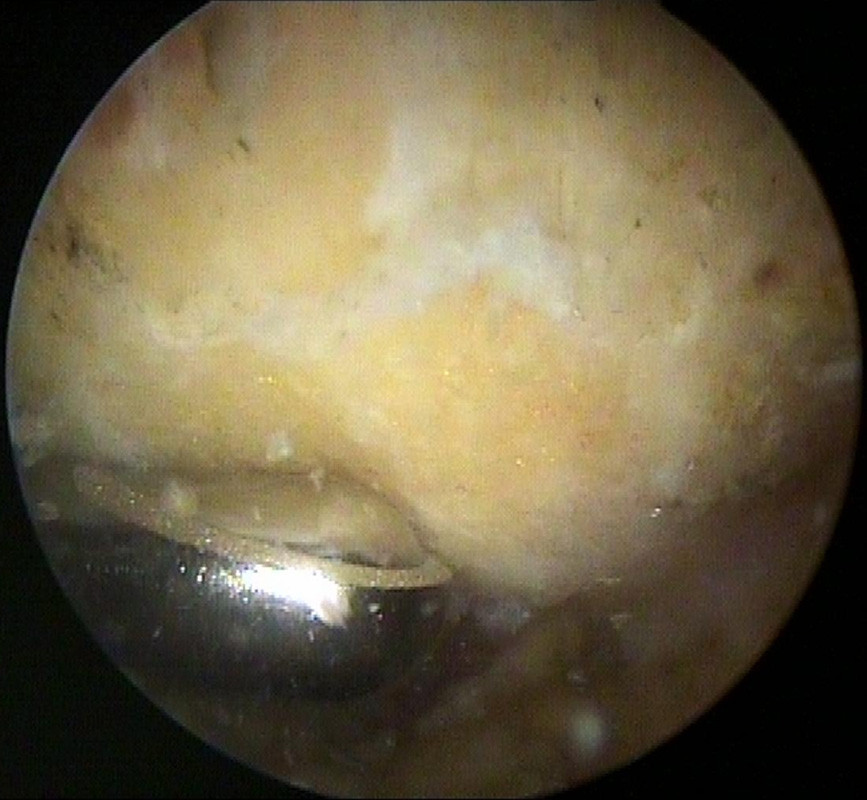

Das Bild links zeigt den nach unter ragenden Knochensporn, das Bild rechts zeigt die unter dem Knochensporn aufgeriebene Sehne und ein Operationsinstrument). Dieser Knochensporn wird dann zunächst von den Weichgeweben befreit und mit dann abgetragen, damit die Unterfläche des Schulterdaches dann glatt und eben ist.